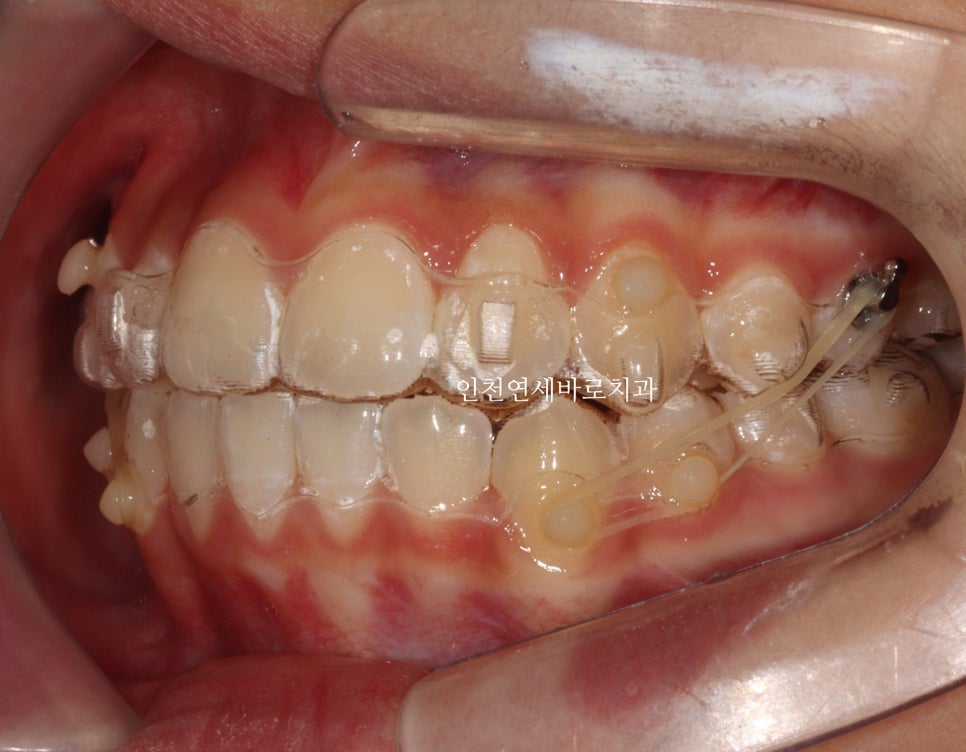

2023.4.18.에 처음 내원해서 23년6월초부터 치료를 시작한 아이입니다.

두번째 치아가 덧니로 있는 경우의 치료는 흔한 경우지만

생각보다 많은 노하우가 필요한 치료라고 생각합니다.

교정 치료 중에 화살표 최후방 치아가 맹출하여,

이 치아를 배열하는 과정에서 치료가 조금 더 길어지긴 했습니다

변수에 대응하는 방법은 여러가지가 있는데 이 친구는 고무줄 사용을 했습니다